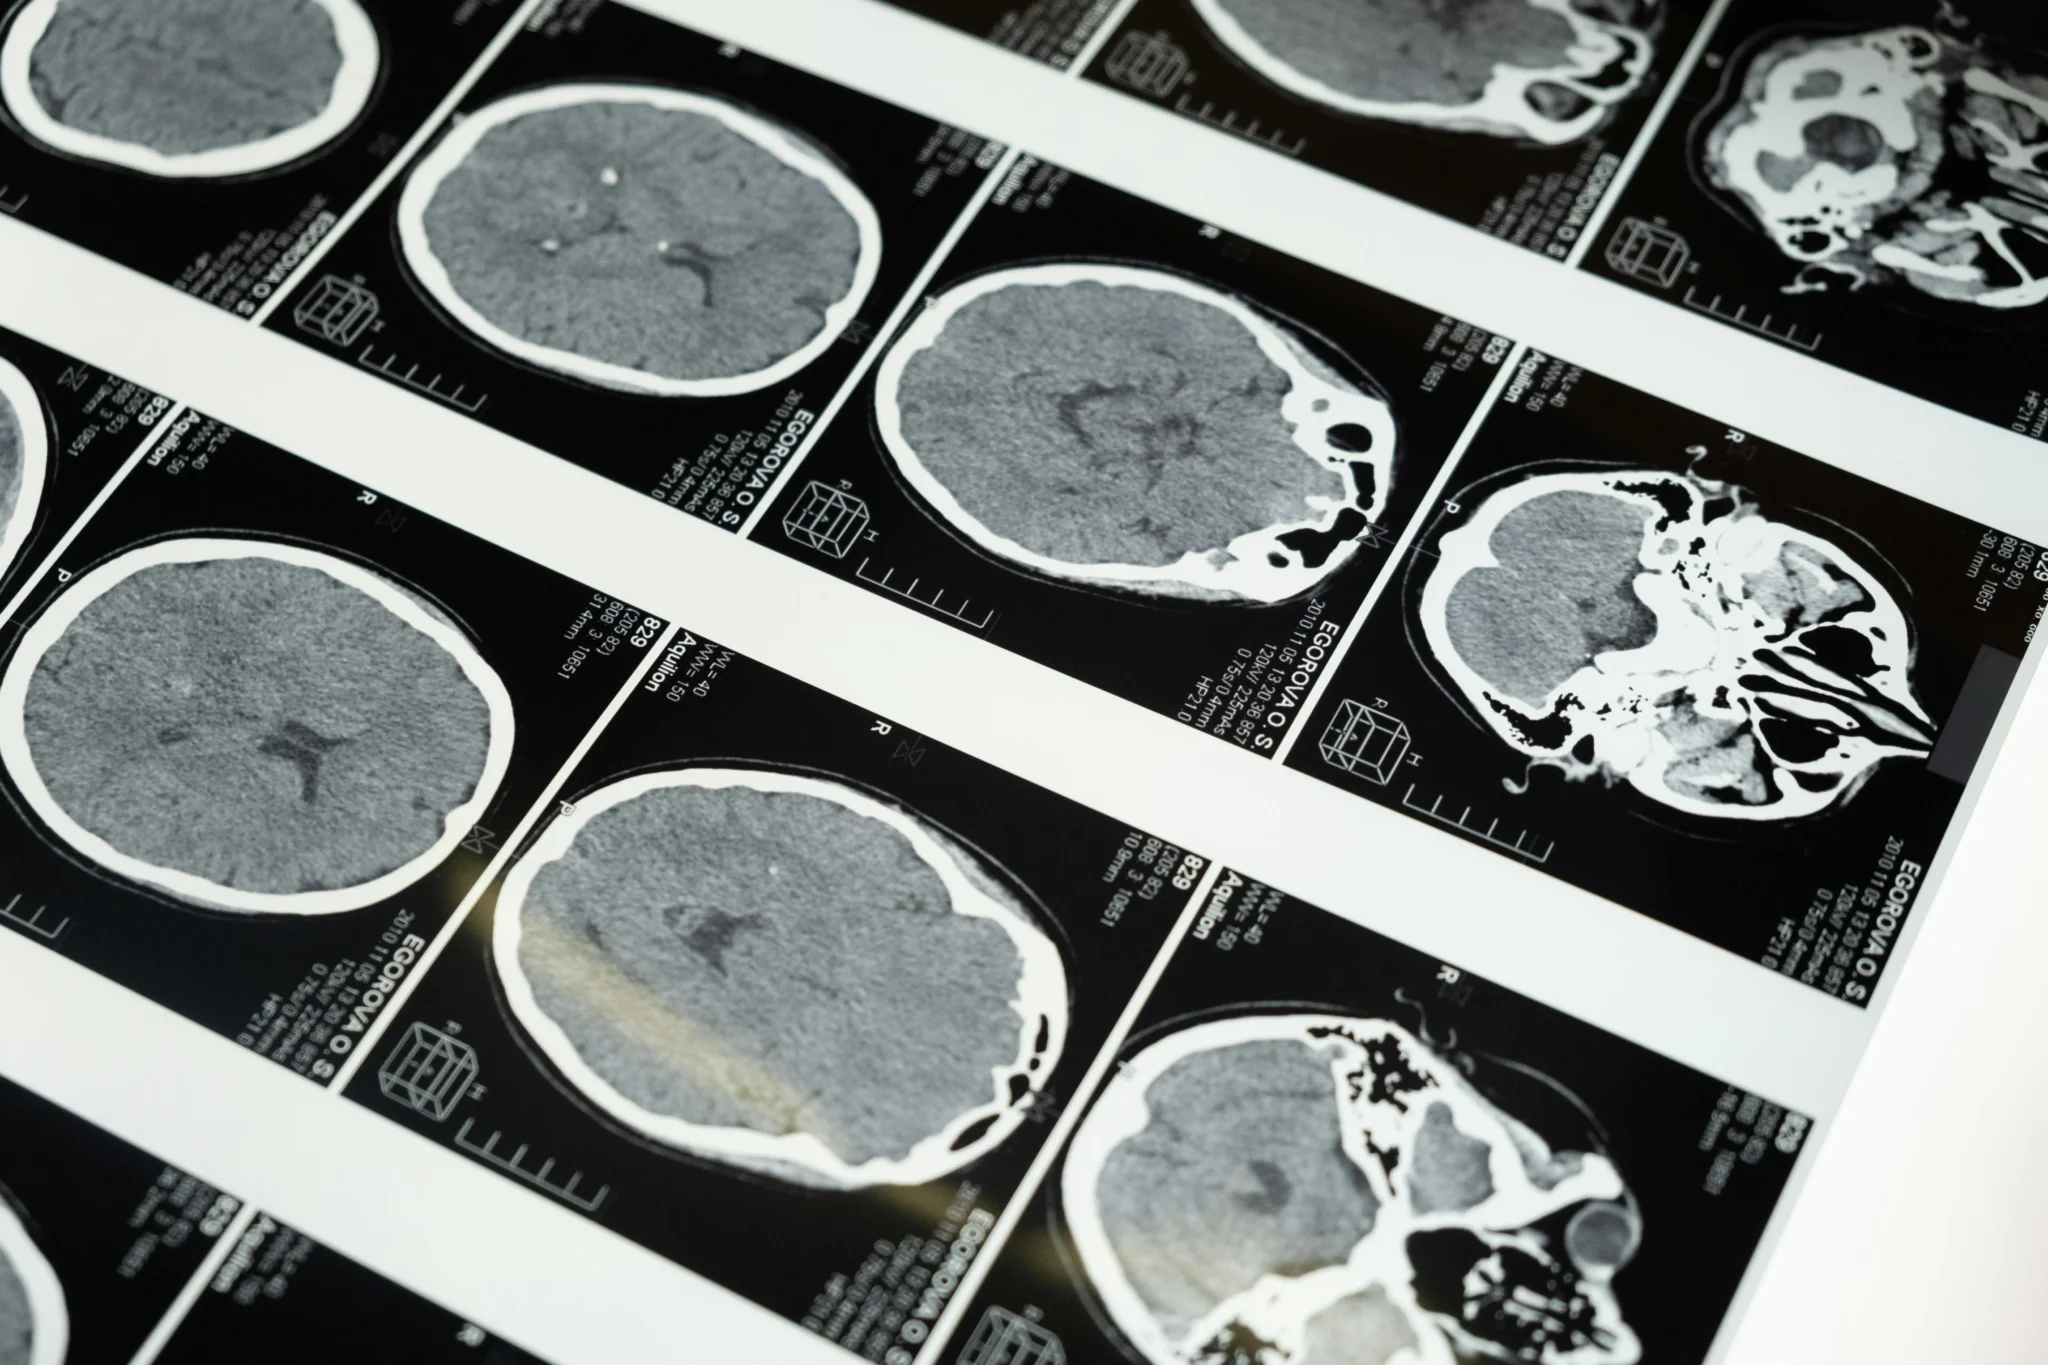

Neurocirurgia Oncológica

A neurocirurgia oncológica é uma especialidade médica que se foca no tratamento cirúrgico de cânceres e tumores que afetam o sistema nervoso, incluindo o cérebro e a medula espinhal. Esta especialidade trabalha em estreita colaboração com oncologistas, radioterapeutas, neurologistas e neurocirurgiões, de forma a oferecer o melhor tratamento possível para o paciente. Muitas vezes, pode ser necessário alinhar a data da cirurgia com outros tratamentos, como quimioterapia e radioterapia, para diminuir o tamanho do tumor antes do procedimento.

Gliomas

Os gliomas são um grupo heterogêneo de tumores cerebrais que incluem os astrocitomas, oligodendrogliomas e ependimomas. São tumores que se originam das células que dão suporte aos neurônios no sistema nervoso central.